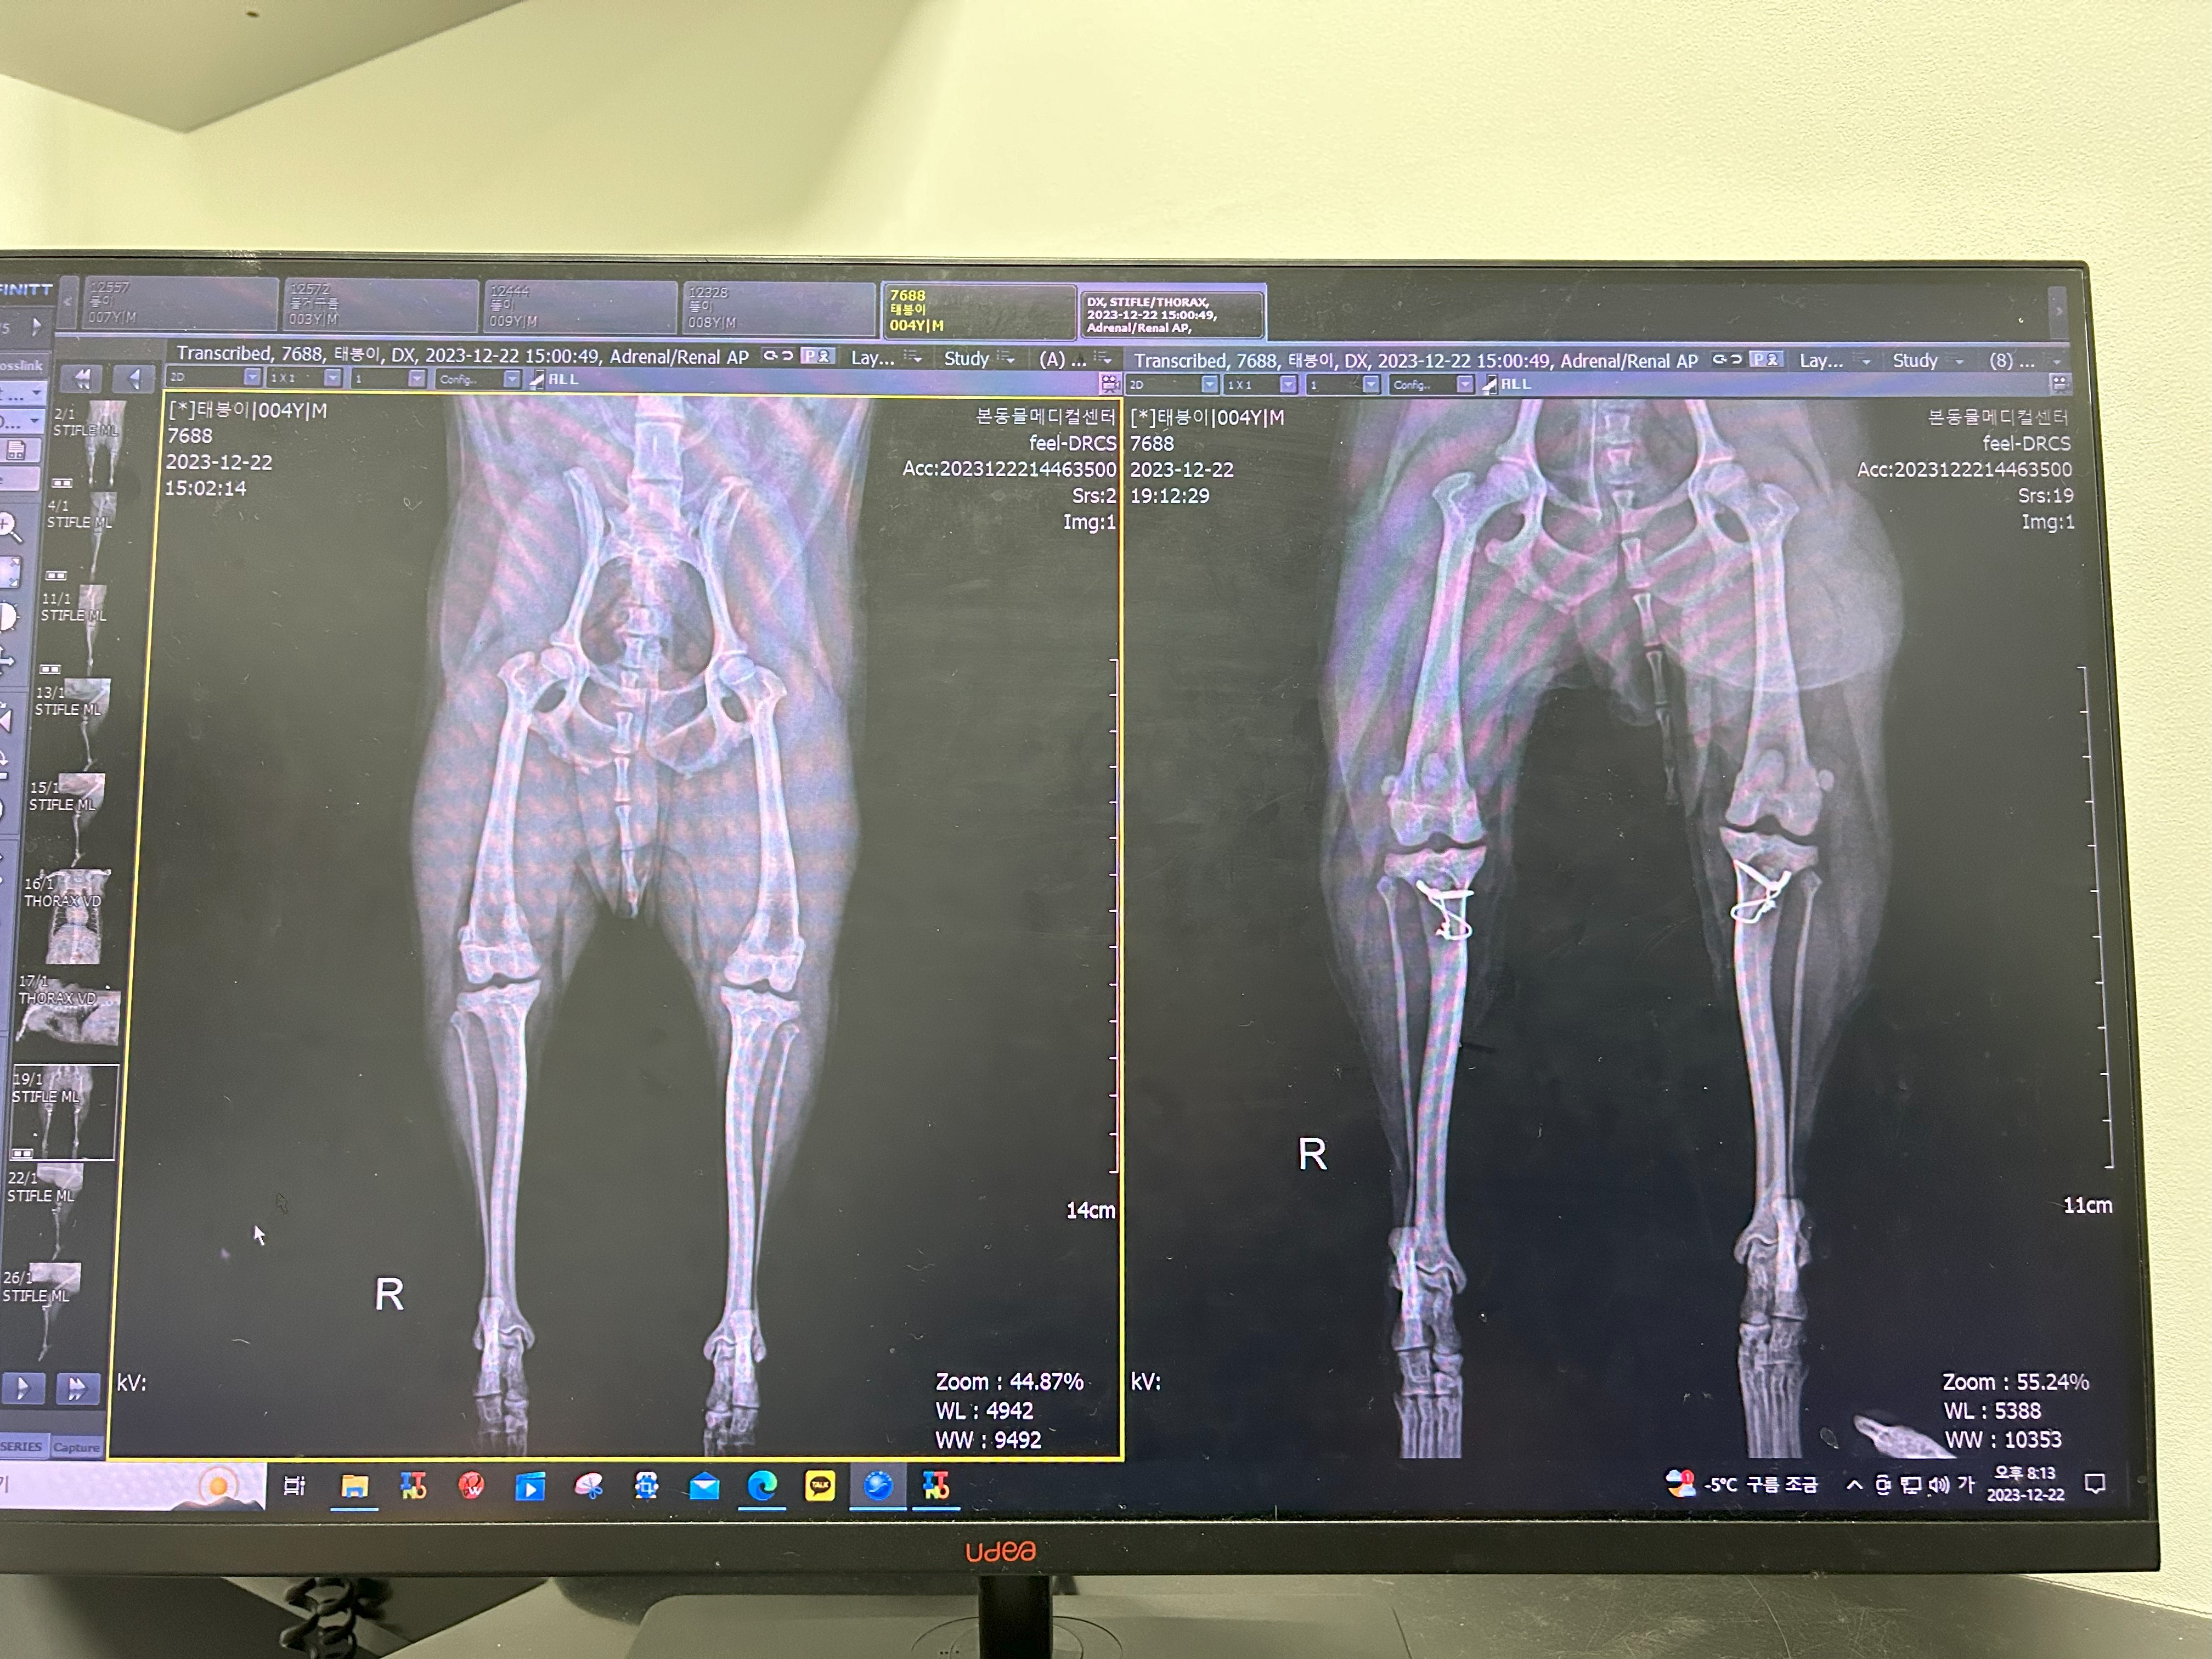

태봉이가 하게 된 강아지 슬개골탈구 수술은 세 가지를 한다고 했어요

제가 전문적인 용어는 잘 몰라서 저의 수준으로 설명을 하자면

소형견들은 무릎뼈를 받쳐주는 뼈의 골이 매우 얕거나 거의 평평해서 경우에 따라 슬개골이 빠지는 경우가 많은데

그 뼈의 홈을 깎아내서 인의적으로 골을 내줘야 합니다.

그래서 그 홈을 깎아내는 수술을 해야 하고

거기에 슬개골이 빠지면서 제자리에 위치하지 못한 슬개골을 제자리에 위치하게 하는 수술,

그리고 와이어로 슬개골을 고정하는 것까지 이렇게 세 가지를 진행했어요